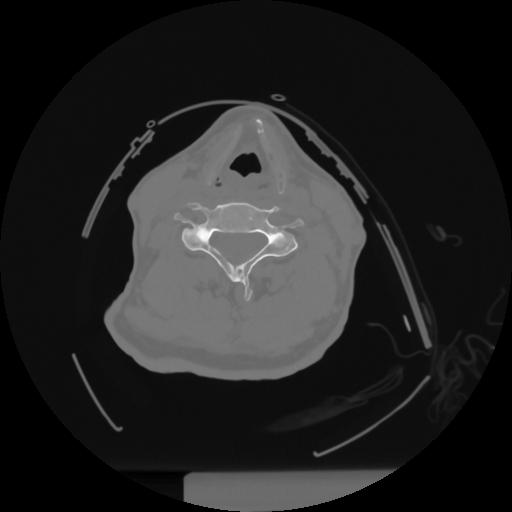

12 P.BLANDAS,,Vol,0.5,P.BLANDAS,,